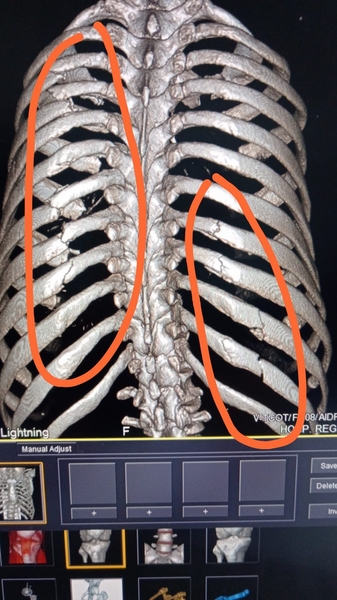

El choque provocó un fuerte golpe en el hombre, por lo que actualmente presenta 11 costillas dislocadas y dos de ellas con fracturas de mucha consideración, por lo que su salud está deteriorada cada día más y se encuentra en riesgo su vida ante la falta de una operación.